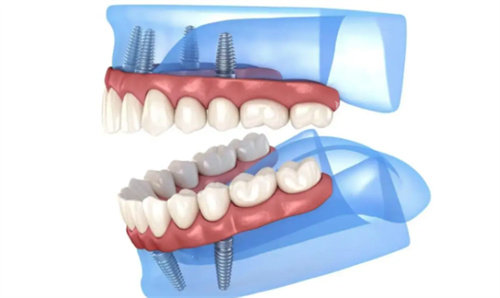

适合All-on-4等即刻负重技术,缩短治疗周期。

Ⅱ类骨 常规圆柱形种植体 All-on-4即刻负重 全口/半口修复